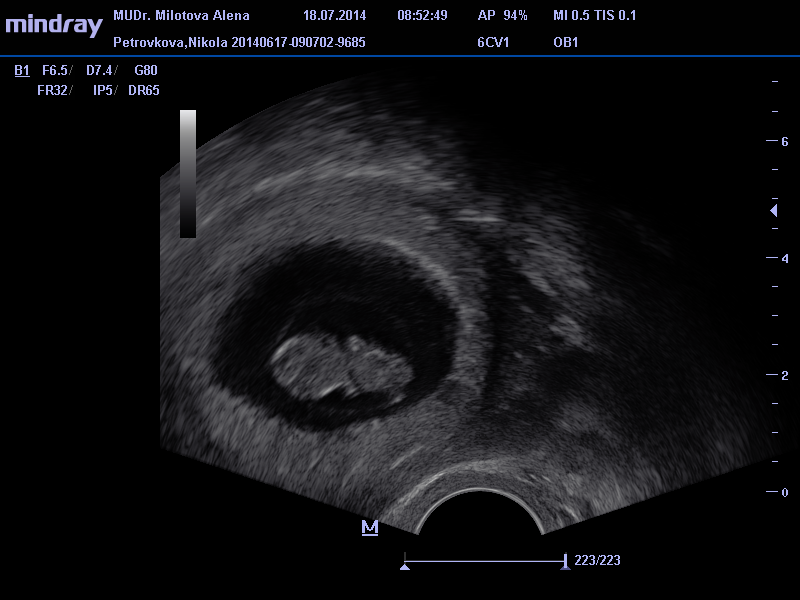

Ahojky holky tak mam po ko a vse v poradku akorad mi broucka nezmerila :( sakra ... Dalsi ko a rovnou zapis a odbery a moc 28.7. :) Mam radost ze pindik malej roste pupiiik :-* posilam i par fotecek :)

tak ted nevim jestli ty fotky vy uvidite :) takze jeste jednou :)